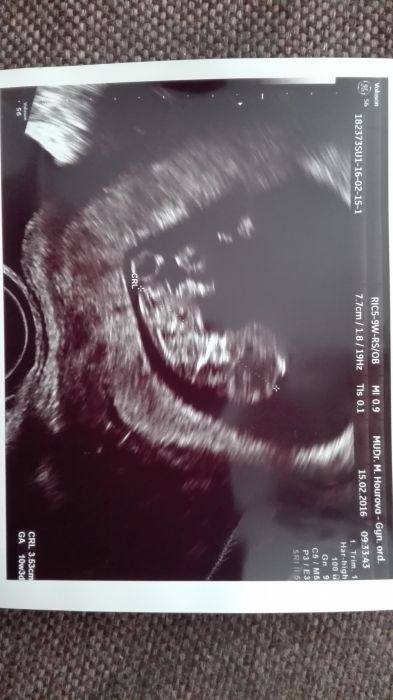

Ahojky devcata, dnes mam za sebou druhou kontrolu, tak jsem dostala i obrazek. Mimco mi zamavalo, bylo to moc krasny :-) vse je v poradku, jen ty nevolnosti jsou narocny. Tady mate forecku, hodne stesti snazilkam preji :-)

Krásný ultrazvuk

[853621] jojo uz mam pekny pupik :-D dnes 10+4

Mysun krásná fotka :)a úžasný malí človíček :-)